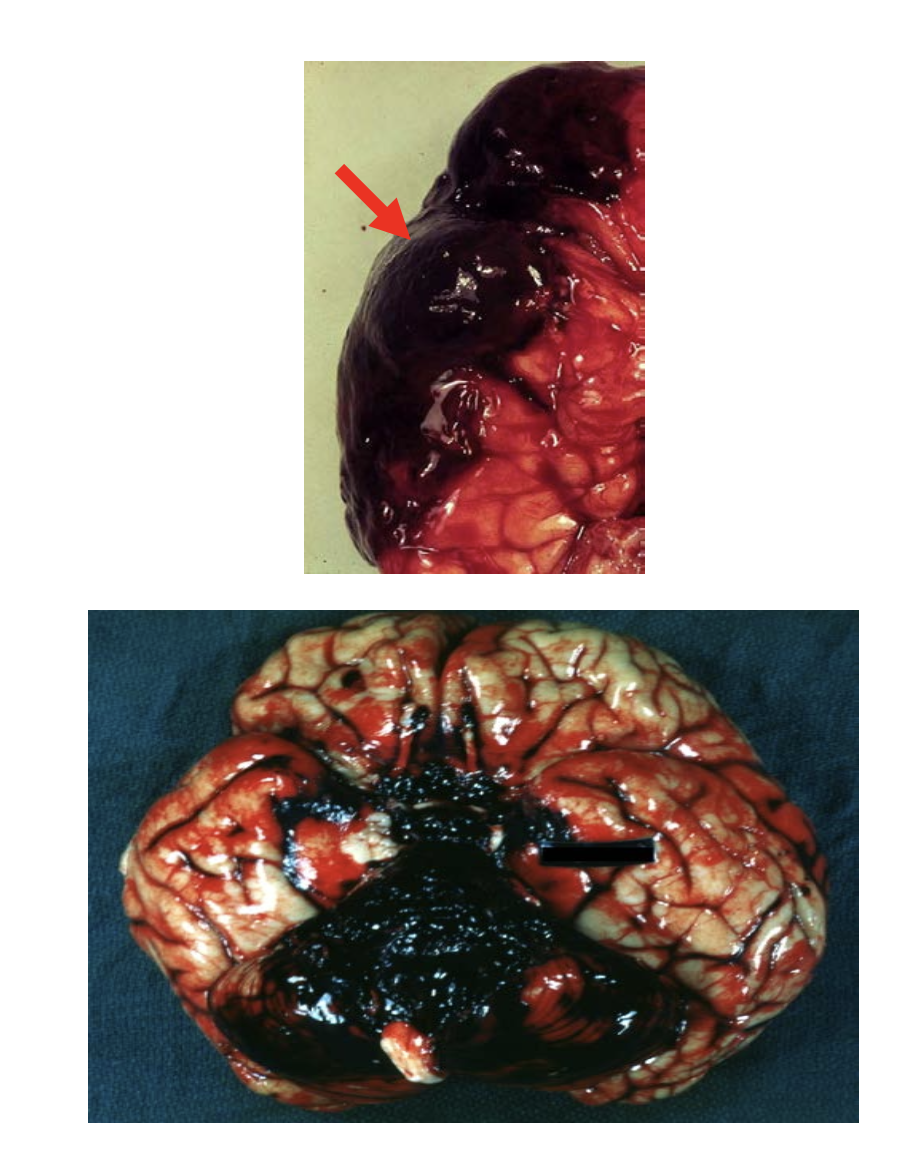

Subarachnoid Hemorrhage

Caused by aneurysmal rupture or trauma

Overlying the blood is the arachnoid membrane (arrow).